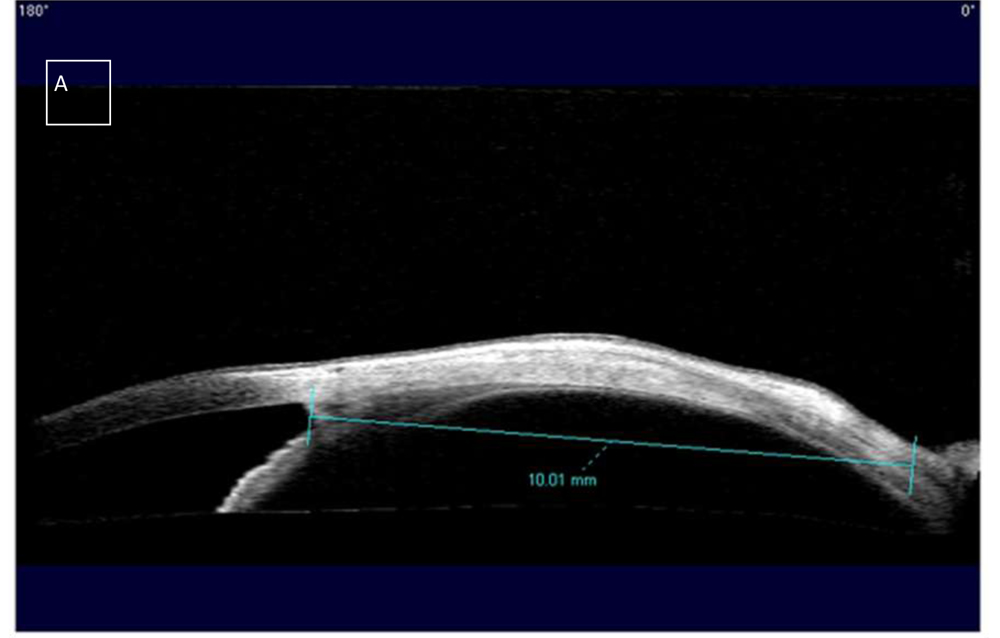

Figure 9 showing agreement between the two methods of measurement

The angle –insertion distance measured with AS-OCT is 10.01mm in this case. Hence the limbus– insertion distance calculated is 11.01mm. B. Intraoperative measurement of limbus –insertion distance with Castroviejo calipers. C. Caliper reading of 11mm.

In a study by Liu et al4, 37 muscles of the 16 patients were studied including 18 medial rectus and 19 lateral rectus muscles.The Bland-Altman plots showed that a total of 17 of 18 (94%) and 18 of 19 (95%) AS-OCT-caliperdifferences, were found in the medial rectus and lateral rectus group respectively, to be within the 95% confidence interval of the mean difference. In addition, 92% of the measured values (34 of 37) were within the predefined level (1.0 mm) of agreement between the two methods. In another study by Ngo et al5, a total of 65 muscles were evaluated, including 9 muscles undergoing reoperation. Of these, 62 muscles were successfully imaged. In all reoperated eyes, the AS-OCT measurements were within 1 mm of the intraoperative measurements. Overall, 89.7% of the measurements were within the 1 mm difference considered clinically acceptable. Our study also showed a good agreement between the two methods. 88.6% of the measurements in our study were within predefined level (1.0 mm) of agreement between the two methods.Ngo et al5also reported that they were able to image a previously recessed muscle as far posterior from the limbus as 13.5 mm. In our study, we could locate a medial rectus muscle recessed 11.01 mm from the limbus.